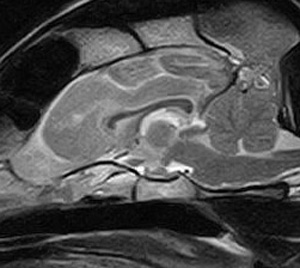

けいれん発作が出るワンちゃんが来院されました。MRI検査では脳に構造上の異常を認めず、特発性てんかんとの診断でお薬での治療となりました。発作は現在のところ、お薬で良好にコントロールされています。